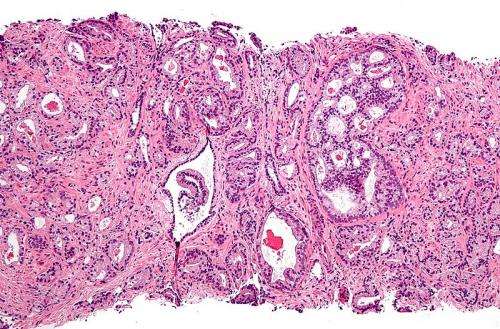

An antibody for treating advanced prostate cancer improves progression-free survival in patients with metastasised, castration-resistant prostate cancer. This is the finding of the long-term analyses of an international phase 3 clinical trial, recently published in the journal European Urology. The study showed that overall survival was two to three times higher than in the placebo arm.

Ipilimumab is a humanized monoclonal IgG1 antibody that is active against CTLA-4. CTLA-4 is a molecule that controls part of the immune system by down-regulating it. “Cancer cells can evade the endogenous defense of the immune system by deactivating it. An antibody that targets CTLA-4, a so-called checkpoint inhibitor (CPI), can block this deactivation, thereby reactivating the immune system once again. This reactivated immune response can then help the body to destroy cancer cells,” explains oncologist Michael Krainer from the Department of Medicine I at MedUni Vienna/Vienna General Hospital and from the Comprehensive Cancer Center (CCC). The internationally renowned Urological Tumors working group from the division led by Krainer was invited to participate in the first global clinical phase 3 trial of a CPI in prostate cancer CA184-043, the long-term results of which have now been published in European Urology.

The recent trial included a total of 799 men. It was conducted globally, in the U.S., Canada, South America, Australia and in European countries. Patients were randomized in a 1:1 ratio to receive bone metastasis radiotherapy (a single 8 Gy fraction) followed by either ipilimumab 10 mg/kg or a placebo every three weeks via up to four injections. Although in the first planned analysis, the survival advantage in the treated group was present, it was not significant, whereas the recent analysis shows that long-term survival after three, four and five years is two to three times higher in the immunotherapy arm as opposed to the placebo arm.

Ipilimumab is licensed by the European Medicines Agency to treat melanoma, lung cancer and bladder cancer. However, there is still a lack of reliable data for approval to treat prostate cancer, since the first planned analysis did not show any significant survival advantage. In the light of the new long-term results, Krainer says, “Immunotherapy is highly promising and can be used, for example, when chemotherapy options have been exhausted or are undesirable. It can also be expedient to start it at an early stage, since any treatment is more effective if there is little cancer present and the patient is in good general health. We are the first group in Austria to gain such valuable experience and we are now attempting to incorporate immunotherapy into the treatment in the context of international clinical trials.”